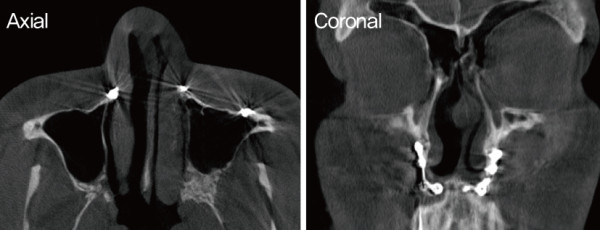

![]()

비중격 및 비밸브 교정 전. 연골부 일부가 이전 양악수술로 인해 소실된

모습이다. 비중격이 전체적으로 좌측 만곡되어 C-shape deviation이

확인되었다.

수술장 소견상 비중격 연골부 일부가 이전 양악수술로 인해 소실된 모습이 보였고, 전체적으로 좌측으로 만곡된 C-shape deviation이 확인되었다. 또 한 비익연골의 내전과 비중격 미단부의 변형으로 인해 좌측 비밸브 부위가 좁아져 있음이

관찰되었다.